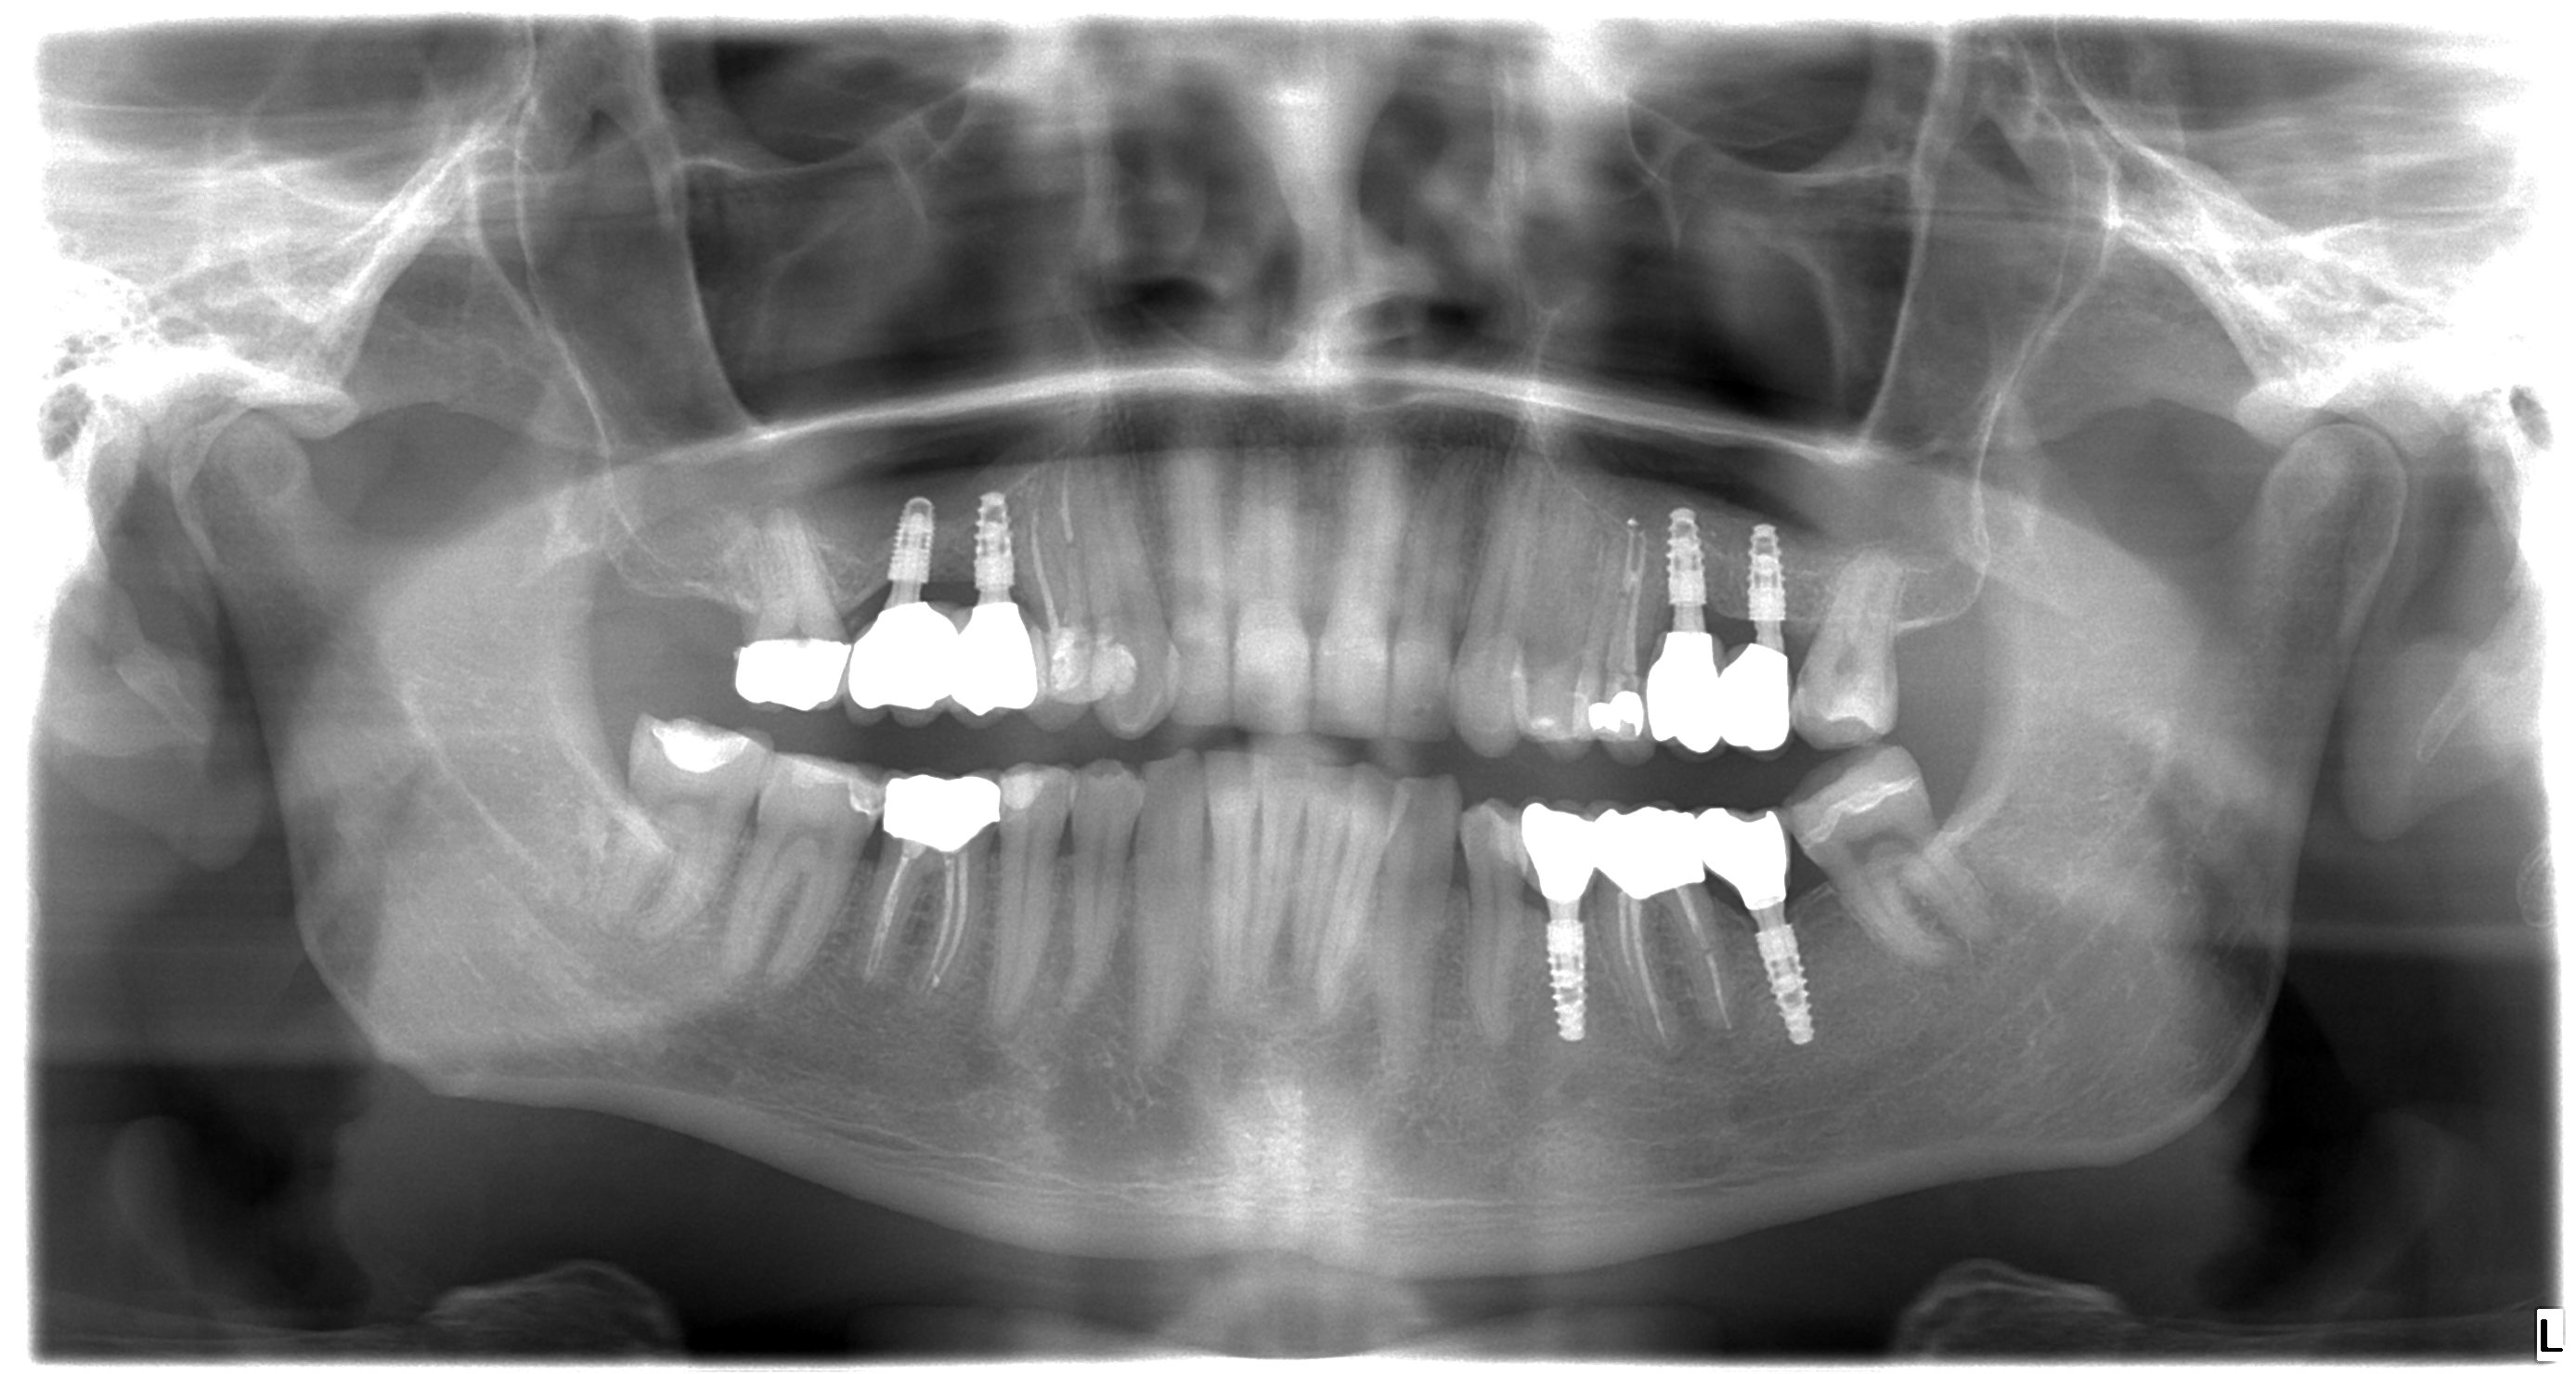

The surgery began with the extraction of tooth number 26 and bone graft on the upper jaw. It continued with implantation on 27, 26, 16 and 15 on upper jaw and 35 and 37 on lower jaw.

3,5 months after implantation, Mr. Peter returned to our dental clinic to continue his treatment with four re-root canal procedures. Doctor decided to gave the implants more time for healing so the patient returned in 2 months to get his front natural teeth reshaped and get impressions for his future implant crowns and zirconium dental crowns.